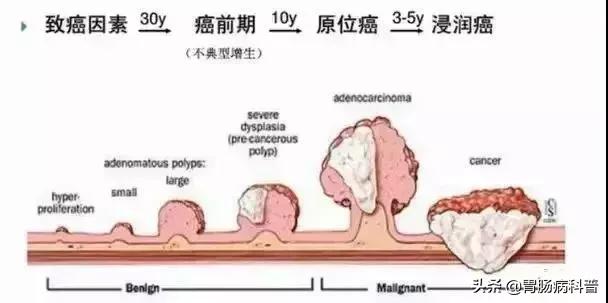

肠息肉演化为肠癌的过程需要5-15年

从正常粘膜到肠癌是个漫长的过程

结肠息肉与结肠癌的关系密切,大约80-95%的结直肠癌是结直肠息肉演变而来。